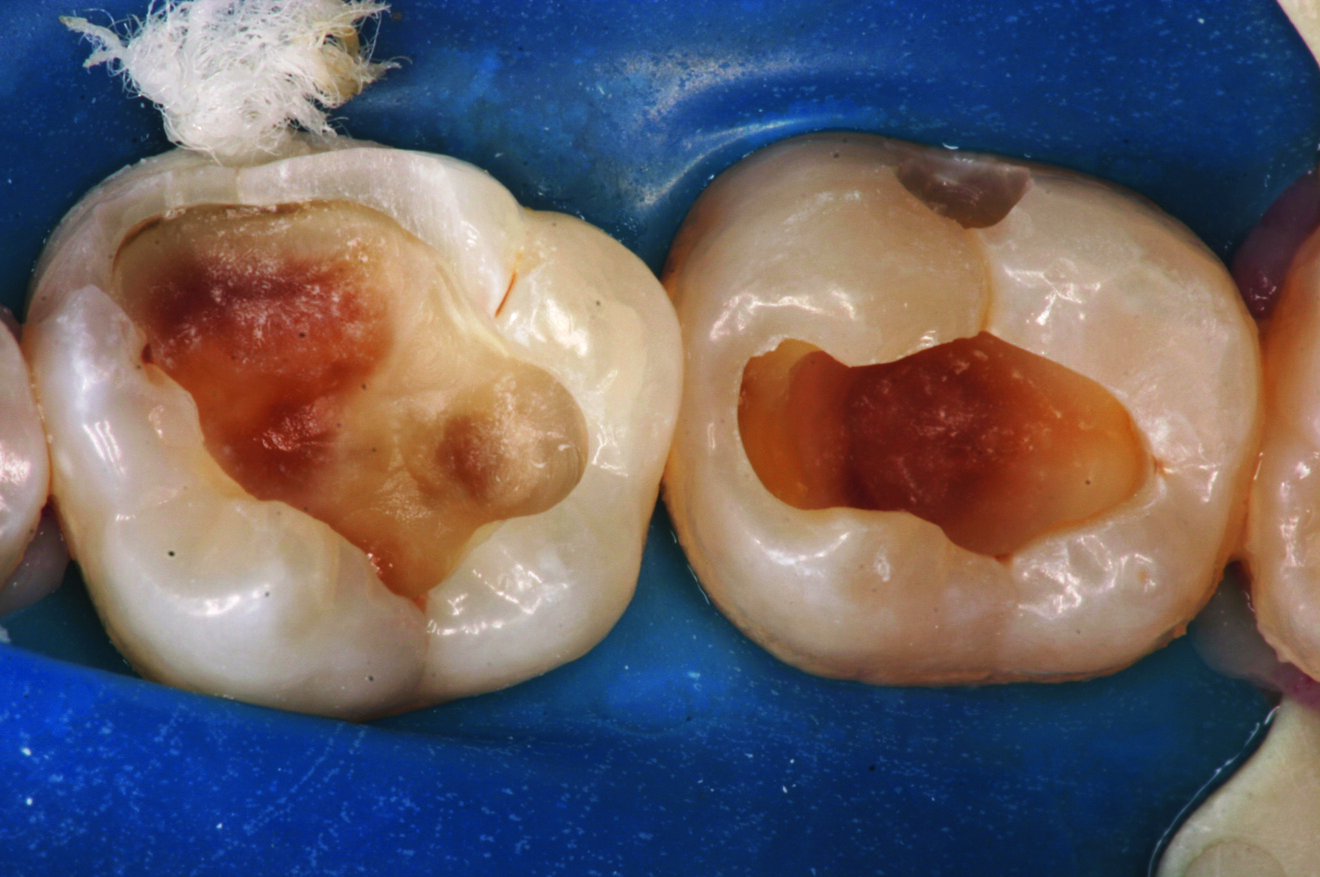

Fig. 2 : Cavité profonde après excavation de la carie.

La cavité occlusale sur 36 qui était de taille moyenne a été restaurée au cours de la même séance à l’aide d’un composite en méthode directe. En revanche sur 37, la cavité profonde a été entièrement reconstituée selon l’approche Bio-Bulk Fill, en utilisant Biodentine comme matériau de coiffage du fond de la cavité juxta pulpaire jusqu’en haut. Après le temps de prise initial de 12 à 15 minutes, la digue a été déposée et l’occlusion délicatement vérifiée à l’aide d’un papier articulé.

Après la mise en place de la digue pour garantir un champ propre et empêcher toute contamination salivaire et bactérienne pendant l’excavation de la carie. Une fraise ronde en carbure de tungstène sur contre-angle bague bleue (1:1) a été utilisée à vitesse et pression faibles pour éviter de surchauffer les tissus pulpaires. La figure 11 montre la cavité préparée après l’élimination des caries ainsi que la pulpe visible par transparence.